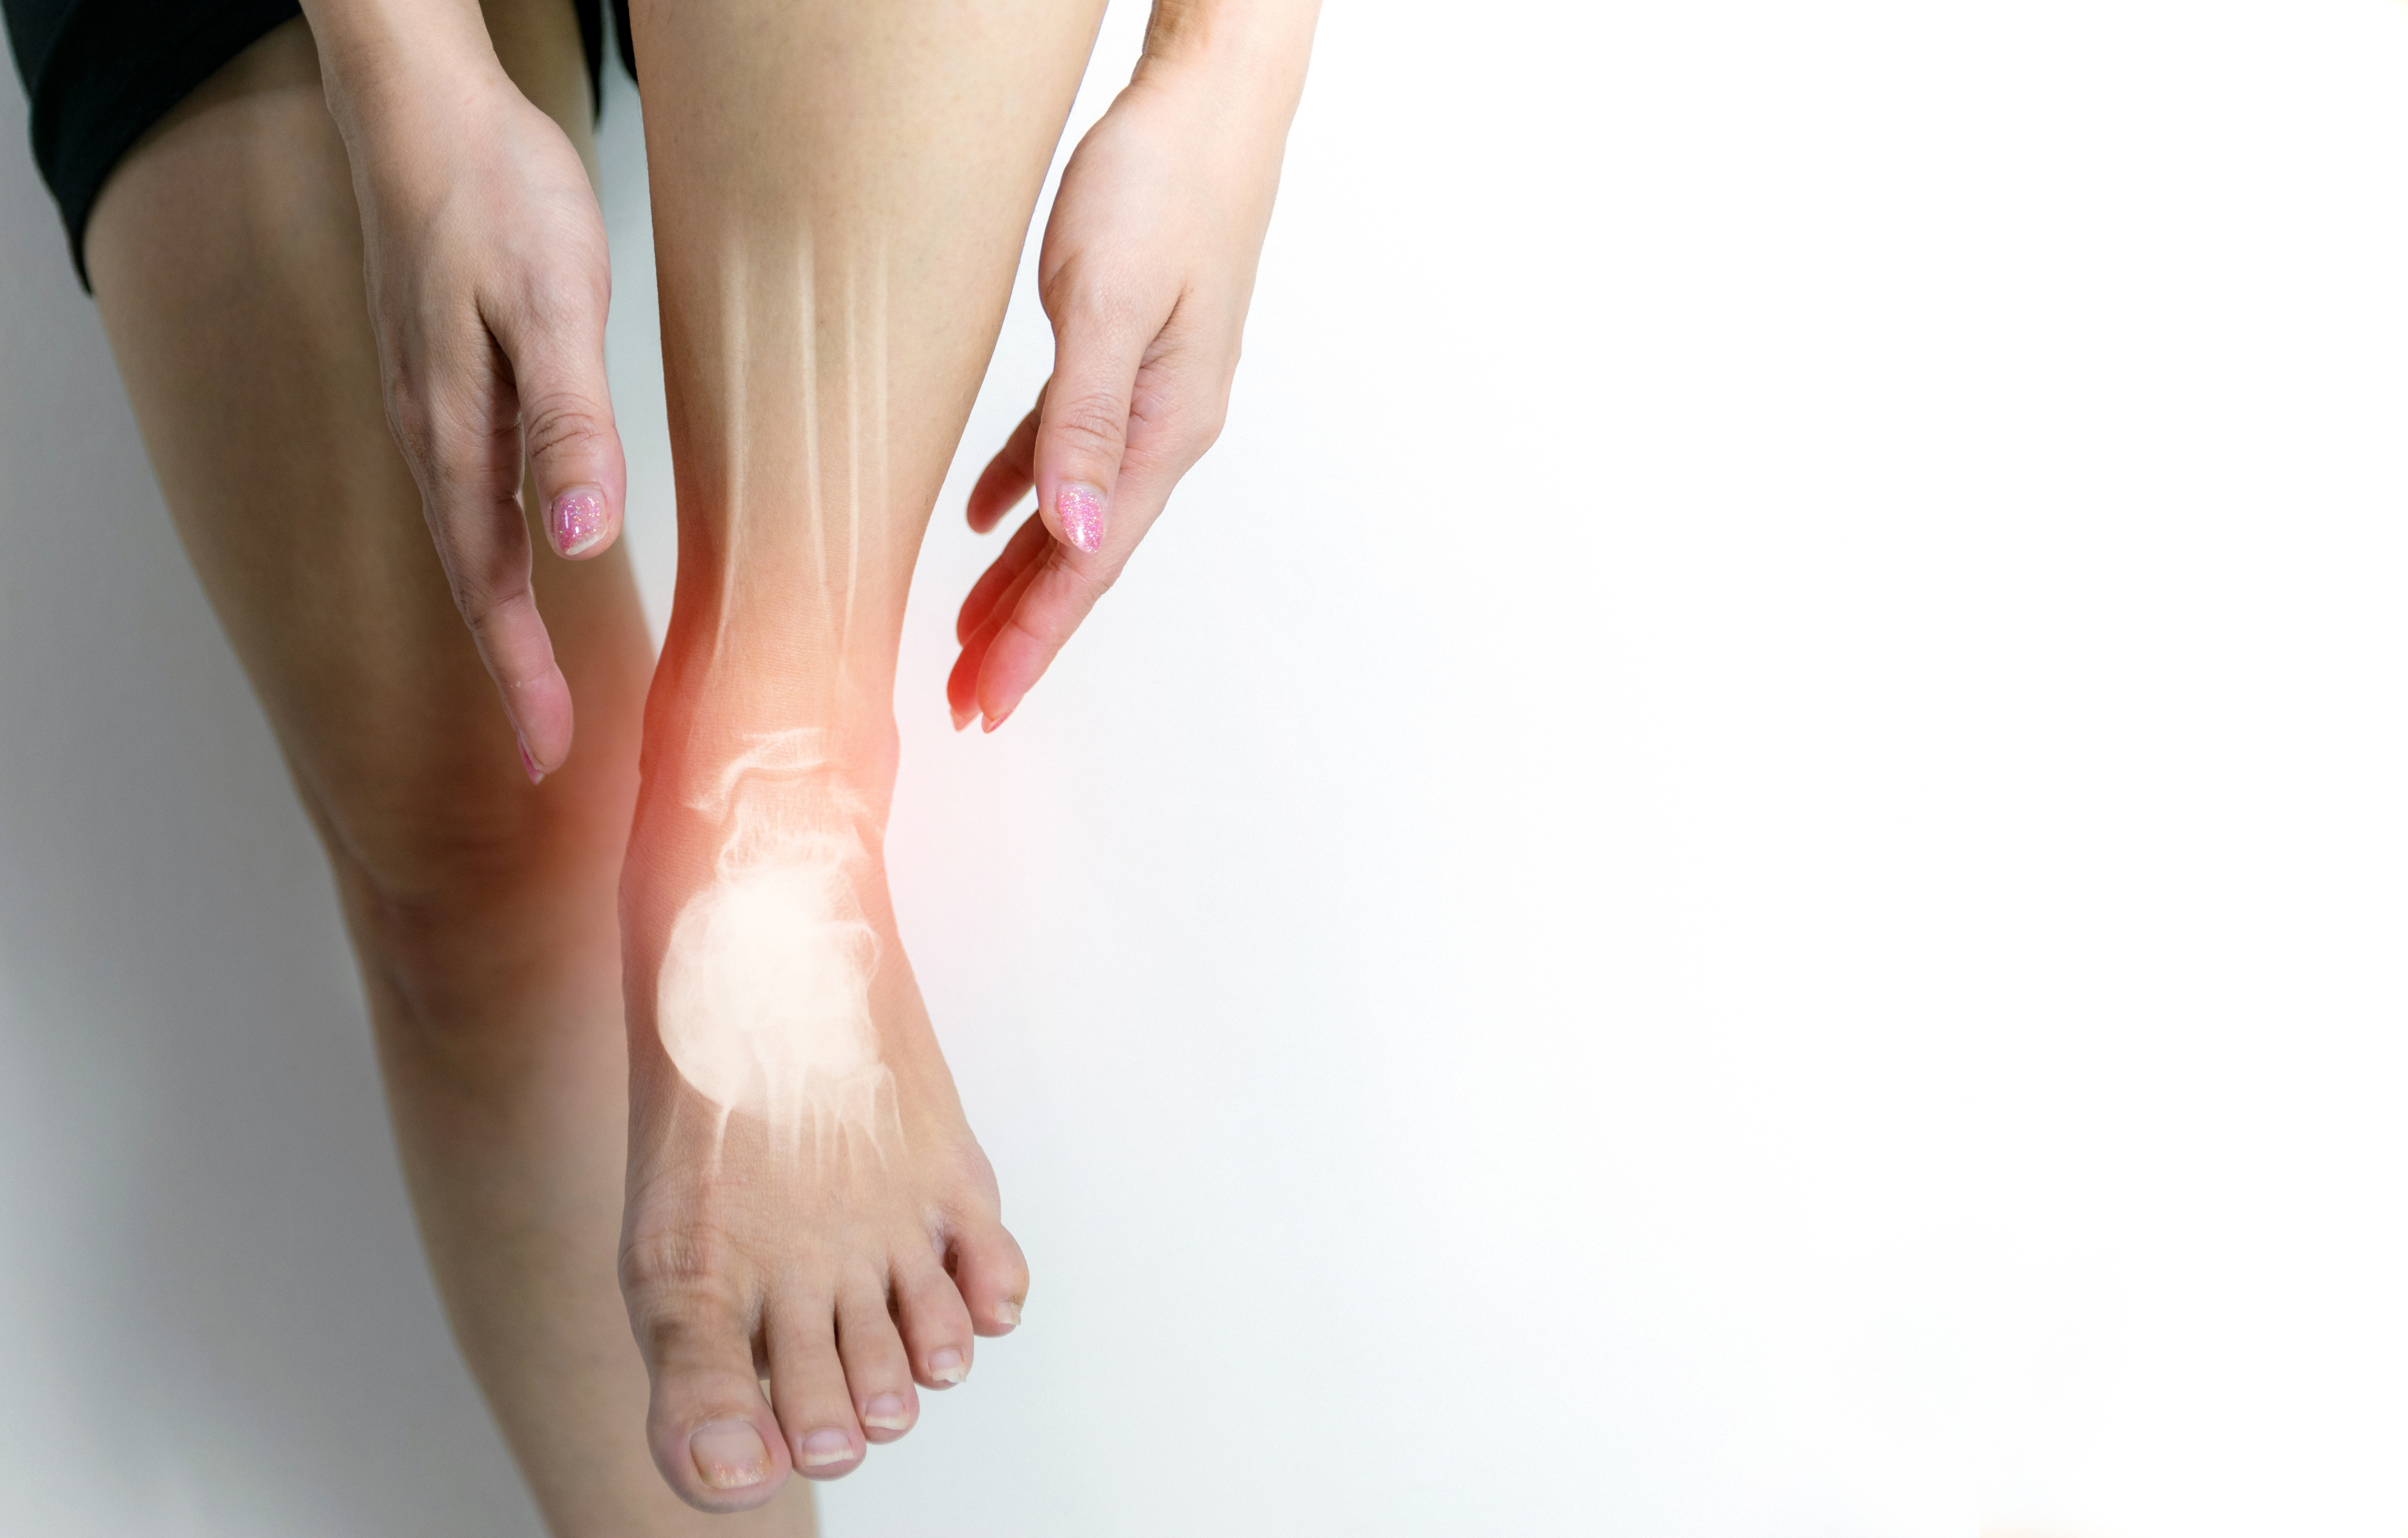

教学病例:踝关节X线片!

高清图普:足踝部解剖及影像学,基础必备!